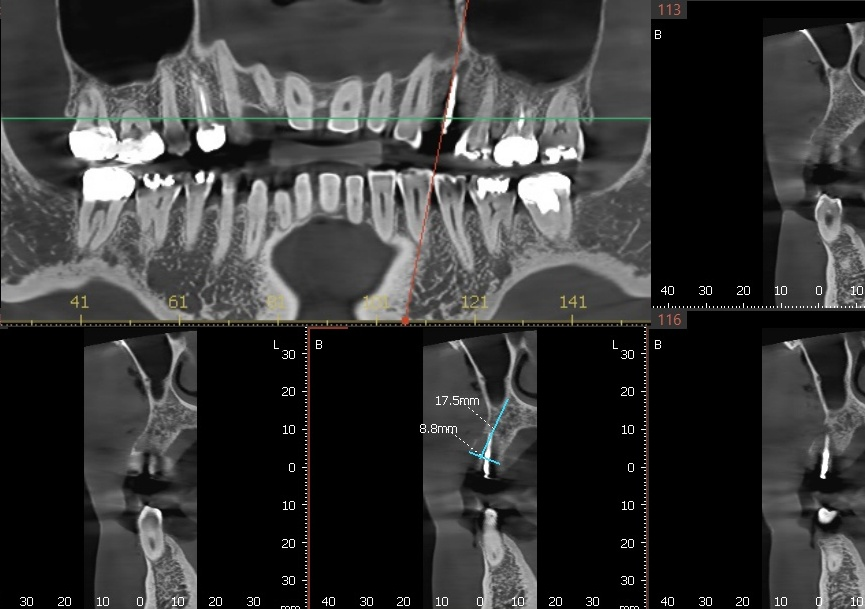

식립 위치에 가이드 핀을 꽂은 상태에서

3D-CT 촬영하여

식립 위치와 기울기를 확인합니다.

아직 발치와의 뼈가

단단히 차지 않은 상태라,

치조골이 약한 쪽으로 핀이 밀린 것으로 확인됩니다.

따라서, CT 상에서 방향을 약간 수정한 뒤

잇몸 절개 없이 핀상방에서

드릴링 하여 정확한 위치에

임플란트 수술을 마칠 수 있습니다.